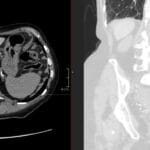

- Radiology Cases: Images with a to-the-point discussion highlighting the specific diagnostic criteria.

- Radiology Case of the Day Collection: Aunt-Minnie Board Cases for Rapid Review.

- Radiology Spotters: 700+ spot / “Aunt-Minnie” cases divided into sets of 10 each!